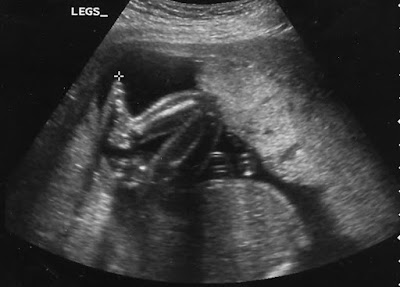

Images of the little girl who will make her grand entrance in 6 +/- 2 weeks. From my perspective, she'll make her exit. Her little legs have been busy kicking me. These images were from early April.

Today, the baby is about 21 weeks old. The first ultra sound revealed that it's a girl! Here's looking forward to pink bows, puffed sleeves, and tea parties! I think she's going to look like John and will have lots of hair when she's born.